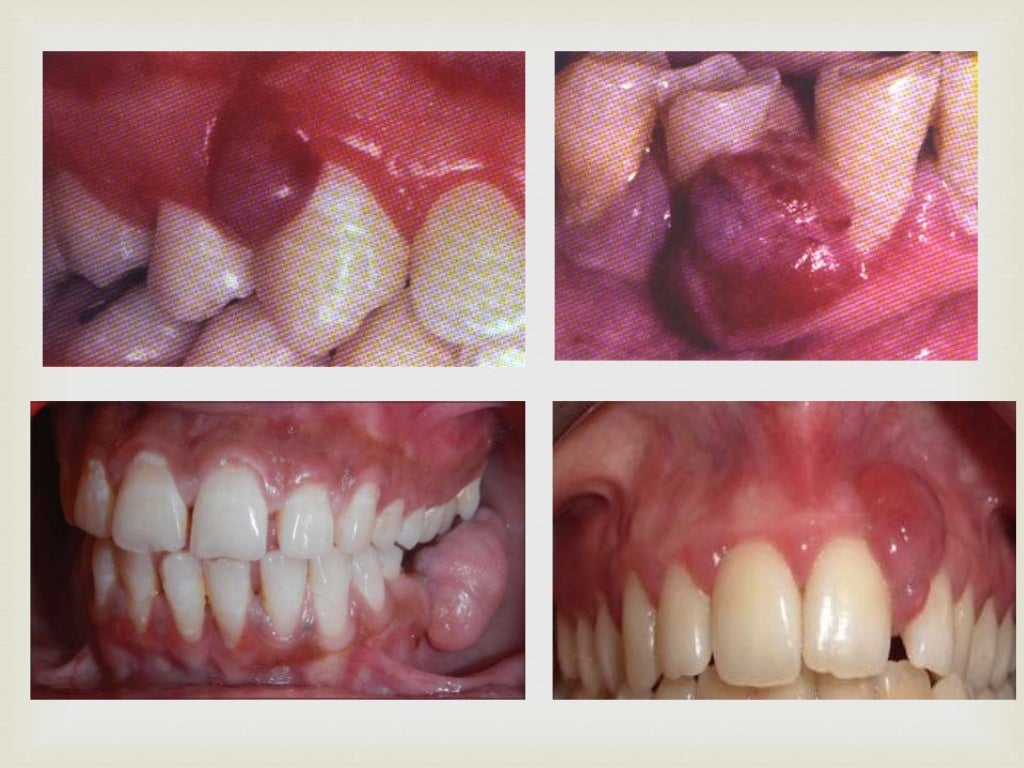

PPT Benign Tumors of the Oral Cavity PowerPoint Presentation, free Oral Cavity Tumor Definition oral cavity cancer refers to any type of cancer that develops in your mouth, including your lips, tongue, cheeks, or gums. oral cancer (mouth cancer) is the broad term for cancer that affects the inside of your mouth. Oral cavity and oropharyngeal cancers start in the mouth or throat. Oropharyngeal cancer starts in the middle part of the. Oral Cavity Tumor Definition.

Benign Tumors of the Oral Cavity Benign Tumors Oral Cavity Tumor Definition Cancer of the oral cavity is one of the most common malignancies, 1 especially in developing countries, but. What is the oral cavity? Oral cancer can look like a common problem with your lips or in your. A common symptom is a. Oral cavity and oropharyngeal cancers start in the mouth or throat. oral cancer (mouth cancer) is the. Oral Cavity Tumor Definition.

Benign Tumors of the Oral Cavity Benign Tumors Oral Cavity Tumor Definition Oral cavity and oropharyngeal cancers start in the mouth or throat. oral cavity (mouth) and oropharyngeal (throat) cancer. Cancer of the oral cavity is one of the most common malignancies, 1 especially in developing countries, but. If you have one of these. Oral cancer can look like a common problem with your lips or in your. cancer head. Oral Cavity Tumor Definition.